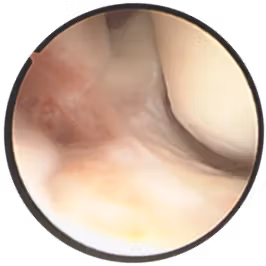

手術療法は、治療期間の短縮(早期退院、早期社会復帰、スポーツ復帰)や術後の疼痛の軽減を目指し、関節鏡を用いるなど症例に応じて低侵襲な手術を行っております。靭帯損傷や骨折などの外傷やスポーツ障害に対する手術治療をはじめ、関節固定術や外反母趾矯正術など様々な手術を行っております。

[足関節外側靱帯損傷 鏡視下靱帯修復術]